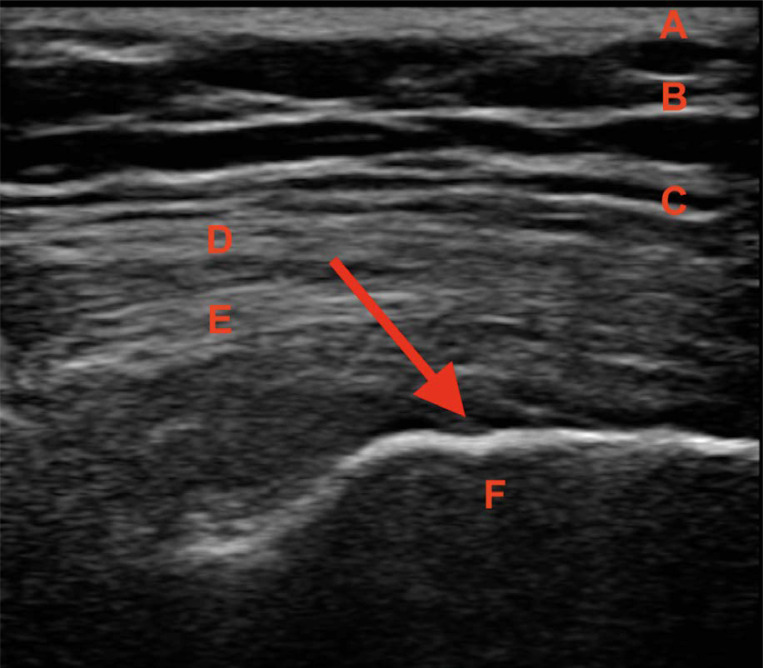

大转子疼痛综合征(GTPS)发生在一大群患者中。这个问题可以影响任何年龄的患者,并且与久坐、超负荷和不符合人体工程学的生活方式/工作方式有关,同时缺乏定期的身体活动。迄今为止的文献描述了各种治疗方法的有效性。使用糖皮质激素注射和物理治疗。其中一种新方法是使用I型胶原蛋白(COL-I)注射胶原蛋白疗法,这是一种源自猪的蛋白质,其目的之一是使炎症改变的肌腱再生。多种修复机制被激活,包括成纤维细胞的诱导和增殖,以及它们向病理部位的迁移。随后是刺激和合成col - 1,分泌和成熟。最终达到再生效果。本文旨在探讨coli作为一种新的治疗手段在GTPS注射治疗中的作用。

Greater trochanter pain syndrome (GTPS) occurs in a large group of patients. This problem can affect patients of any age and is associated with a sedentary, overloading, and non-ergonomic lifestyle/work with a concomitant lack of regular physical activity. The literature to date describes the effectiveness of various therapies. Glucocorticosteroid injections and physical therapy are used. One of the new methods is injection collagen therapy using collagen type I (COL-I), a protein of porcine origin, which aims, among other things, to regenerate inflammation-changed tendon. Various repair mechanisms are activated, including the induction and proliferation of fibroblasts, as well as their migration to the pathological site. This is followed by stimulation and synthesis of COL-I, secretion, and maturation. Ultimately, a regenerative effect is achieved. This article aims to discuss the role of COL-I in the injectable treatment of GTPS as a new therapeutic approach.